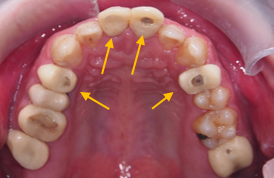

原來我有這麼多問題!?

牙周以及假牙的前置處理

治療前 :前牙錯咬,上下排齒列不整,蛀洞大,左下缺牙空間大。